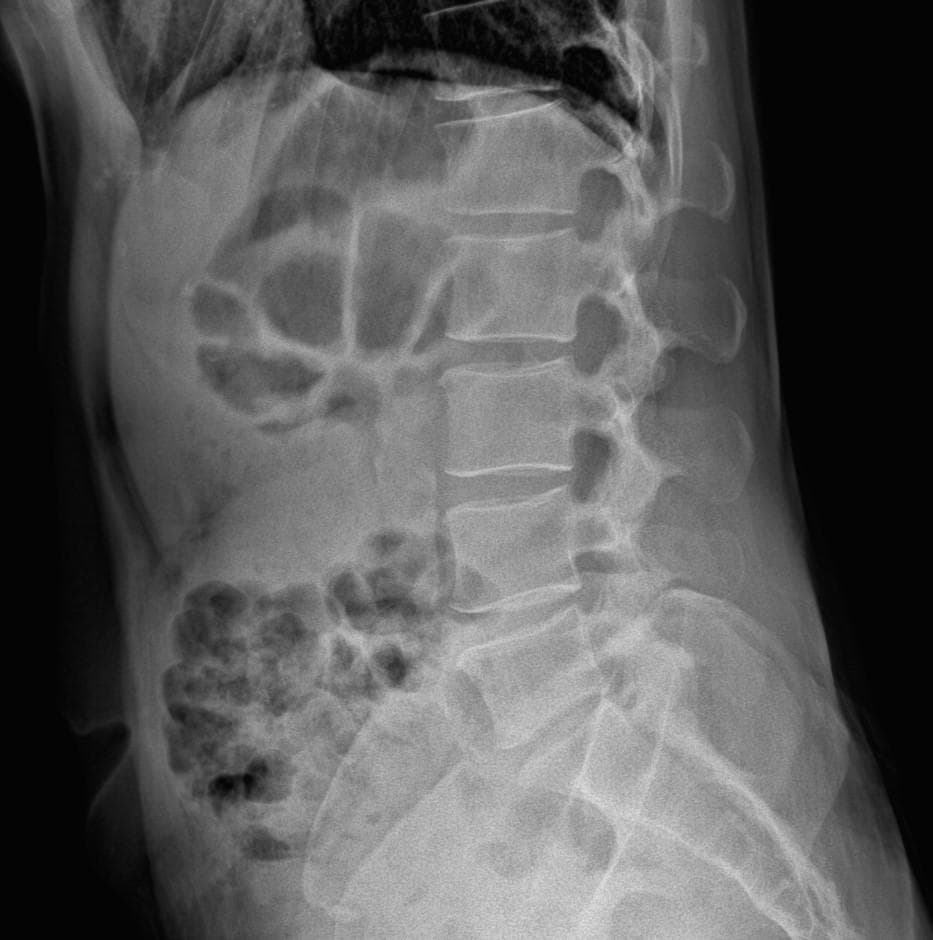

• 1번 째 사진

엑스레이 상에서는 요추 배열이 전반적으로 잘 유지돼 보입니다. 마나 일부 요추 간격이 좁아진 부위가 있어 보입니다. 말씀하신 것처럼 특정 동작에서 찌릿 혹은 뜨끔하거나, 최근 뻐근함이 생기는 건 디스크 초기나 근육, 인대 긴장에서도 나타날 수 있습니다.

허리의 커브가 줄어들어있다는것을 제외하고는 크게 문제가될만한 부분은없는데요 통증과불편감이 지속된다면 MRI와같은 정밀검사가 필요할수있습니다

사진상 요추 사이의 간격이 다소 좁아 보이며 간격이 좁다는 것은 퇴행성 변화를 의미하며 척추의 정렬 또한 큰 전위는 없어 보이나 허리 곡선이 정상보다는 조금 감소한 상태로 이러한 경우 근육의 긴장이나 만성적인 통증이 발생할 수 있습니다.

• 엑스레이 검사를 통해서는 현실적으로 뼈 위주의 평가만 가능하며 정밀하고 자세하게 평가를 내리는 것은 어렵습니다. 올리신 엑스레이 사진들에는 특별히 문제가 있다고 볼만한 소견이 크게 있어보이거나 하지는 않습니다.

우선 현재로썬 척추와 척추 사이인 디스크 공간이 좁지는 않아보이지만 다소 요추의 커브가 감소되어 있어 보입니다.